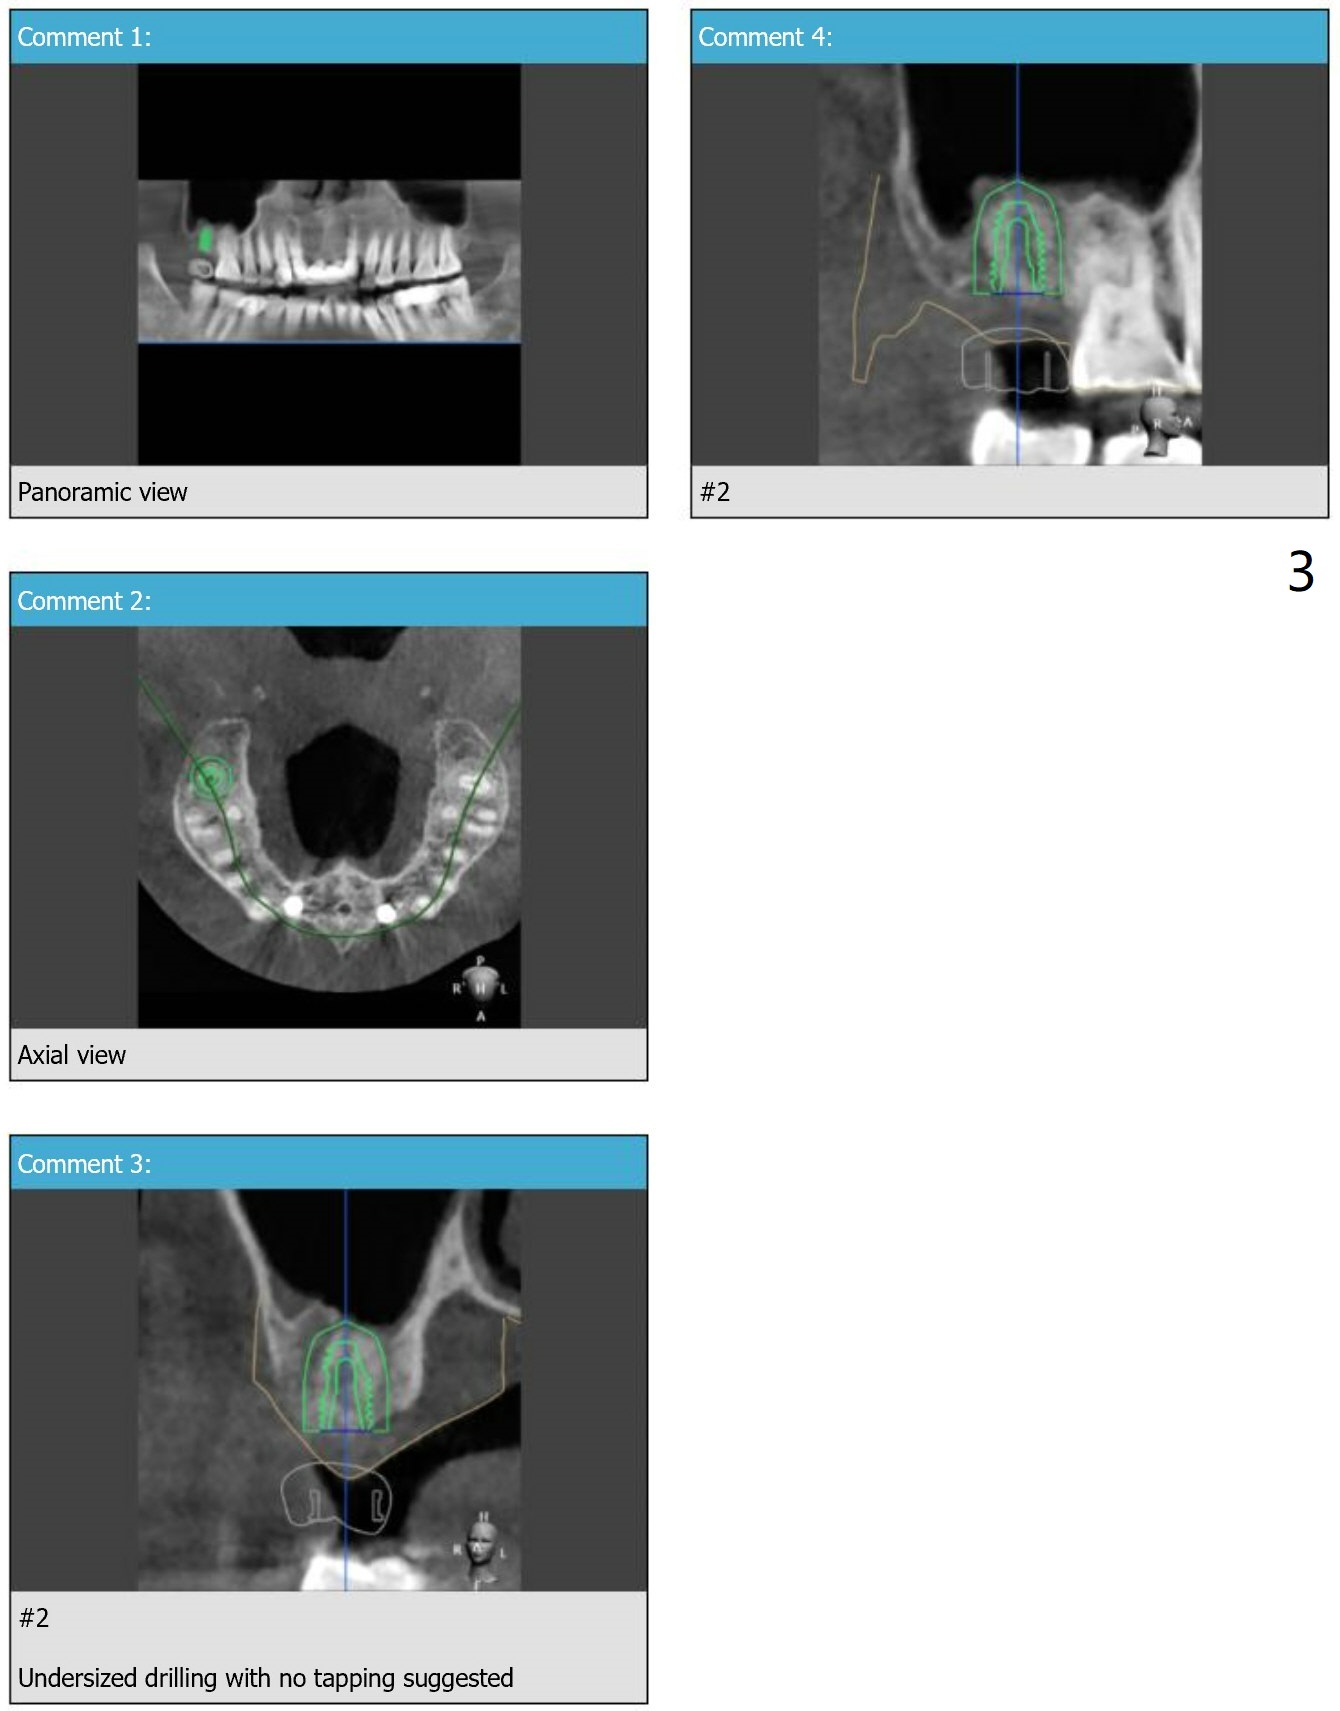

No Sinus Floor No Sinus Lift

Four months post #2 implant removal (without sinus floor) and bone graft, a 5x8.5 mm implant will be placed without sinus lift.

Upper Molar

Immediate Implant,

Trajectory